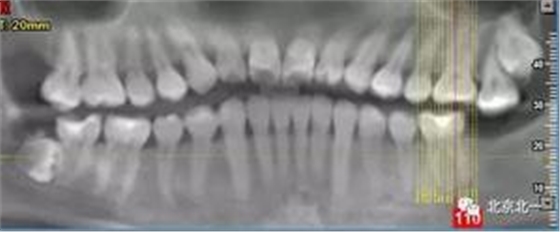

圖二:自帶的CBCT顯示下牙槽神經(jīng)管貼著智齒走形。